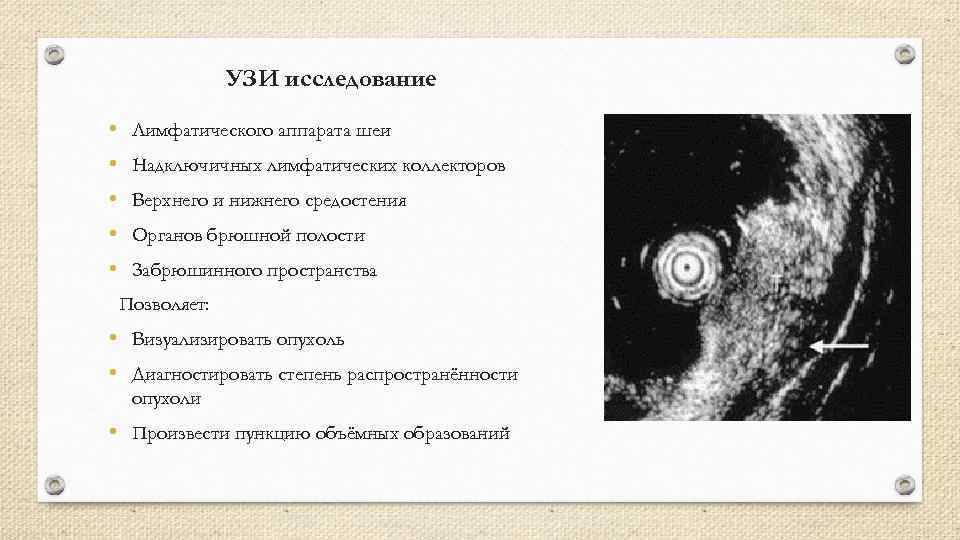

УЗИ исследование • • • Лимфатического аппарата шеи Надключичных лимфатических коллекторов Верхнего и нижнего средостения Органов брюшной полости Забрюшинного пространства Позволяет: • Визуализировать опухоль • Диагностировать степень распространённости опухоли • Произвести пункцию объёмных образований

УЗИ исследование • • • Лимфатического аппарата шеи Надключичных лимфатических коллекторов Верхнего и нижнего средостения Органов брюшной полости Забрюшинного пространства Позволяет: • Визуализировать опухоль • Диагностировать степень распространённости опухоли • Произвести пункцию объёмных образований